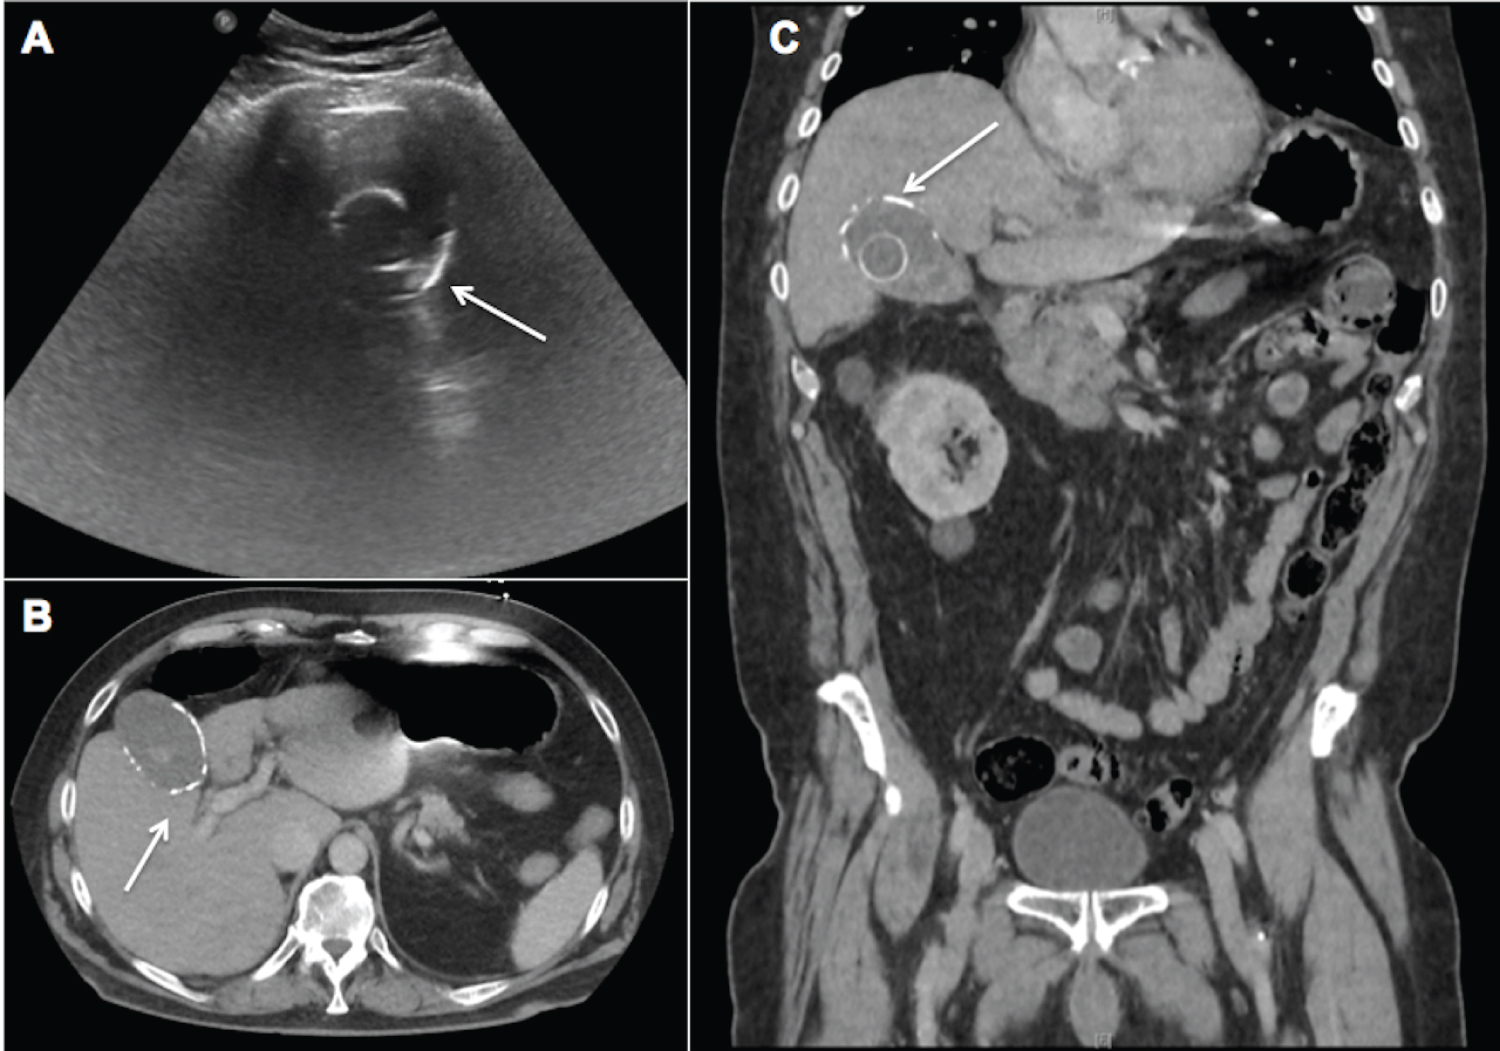

A 68-year-old man with a known history of cholelithiasis presented with worsening epigastric and right upper quadrant discomfort. He was afebrile, with mild leukocytosis (13.3 K/CMM) and normal liver function tests. Ultrasound and CT (abdomen/pelvis) showed cholelithiasis with gallbladder wall calcifications (Figure 1A, Figure 1B and Figure 1C, arrow indicates calcifications) and an incidental 7 cm right renal mass. Patient underwent laparoscopic cholecystectomy in conjunction with laparoscopic radical nephrectomy. Intraoperative findings demonstrated porcelain gallbladder with dense fibrotic adhesions. Pathology of the gallbladder revealed cholelithiasis, chronic cholecystitis with focal high-grade dysplasia and extensive calcified fibrosis of gallbladder wall. Right kidney pathology showed 5.4 cm clear cell renal cell carcinoma (WHO/ISUP Grade 2) with clear margins. The patient had an uneventful recovery. Although historically associated with increased risks of malignancy, the true incidence of malignancy in porcelain gallbladder is thought to be significantly lower than previously reported. Operative management is indicated in symptomatic patients.

Figure 1: Ultrasound of the abdomen (A) demonstrates calcification in the wall of the gallbladder (arrow); which is also documented on CT scan (B & C, arrow). A calcified gallstone is also noted on ultrasound (A) and CT scan (C).